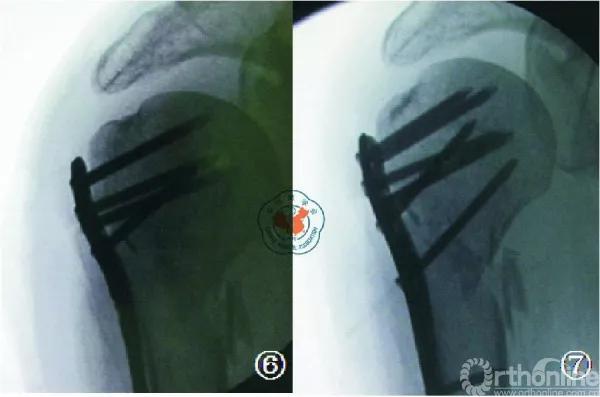

该理论认为:肱骨头下方内侧皮质的支撑作用是防止术后肱骨头塌陷的主要支撑作用。在复位和固定的时候,该部位必须作为重点修复和复位的部分,予以足够的重视。目前认为,在肱骨近端骨折的复位和固定中,肱骨头内下方皮质支撑作用十分重要,应当予以充分复位及支持。如果内侧皮质支撑结构破坏广泛,可采用长短腓骨髓腔内结构性植骨以重建内侧支撑。如内侧皮质结构尚完整,但出现了内侧的阴性支撑,则需要使用肱骨距螺钉斜跨干骺端与后内侧皮质以行支撑(图6、7)。在此强调的是,内侧皮质缺损是肱骨头内翻畸形的力学不稳定因素,但在治疗中首先应将肱骨头复位至正常头干角,再行稳定固定。如复位不良,结构性的支撑植骨只能预防肱骨头的进一步内翻塌陷而并不能起到复位作用,而肱骨距螺钉对内翻畸形的肱骨头则并无保护作用。

图⑥ 示内侧皮质粉碎的肱骨近端两部分骨折(外科颈);

图⑦ 钢板固定后见内侧皮质不连续,肱骨近端骨折在内侧无嵌 插,属阴性支撑。经philos钢板“E”孔打入肱骨距螺钉,起内侧支撑作用。